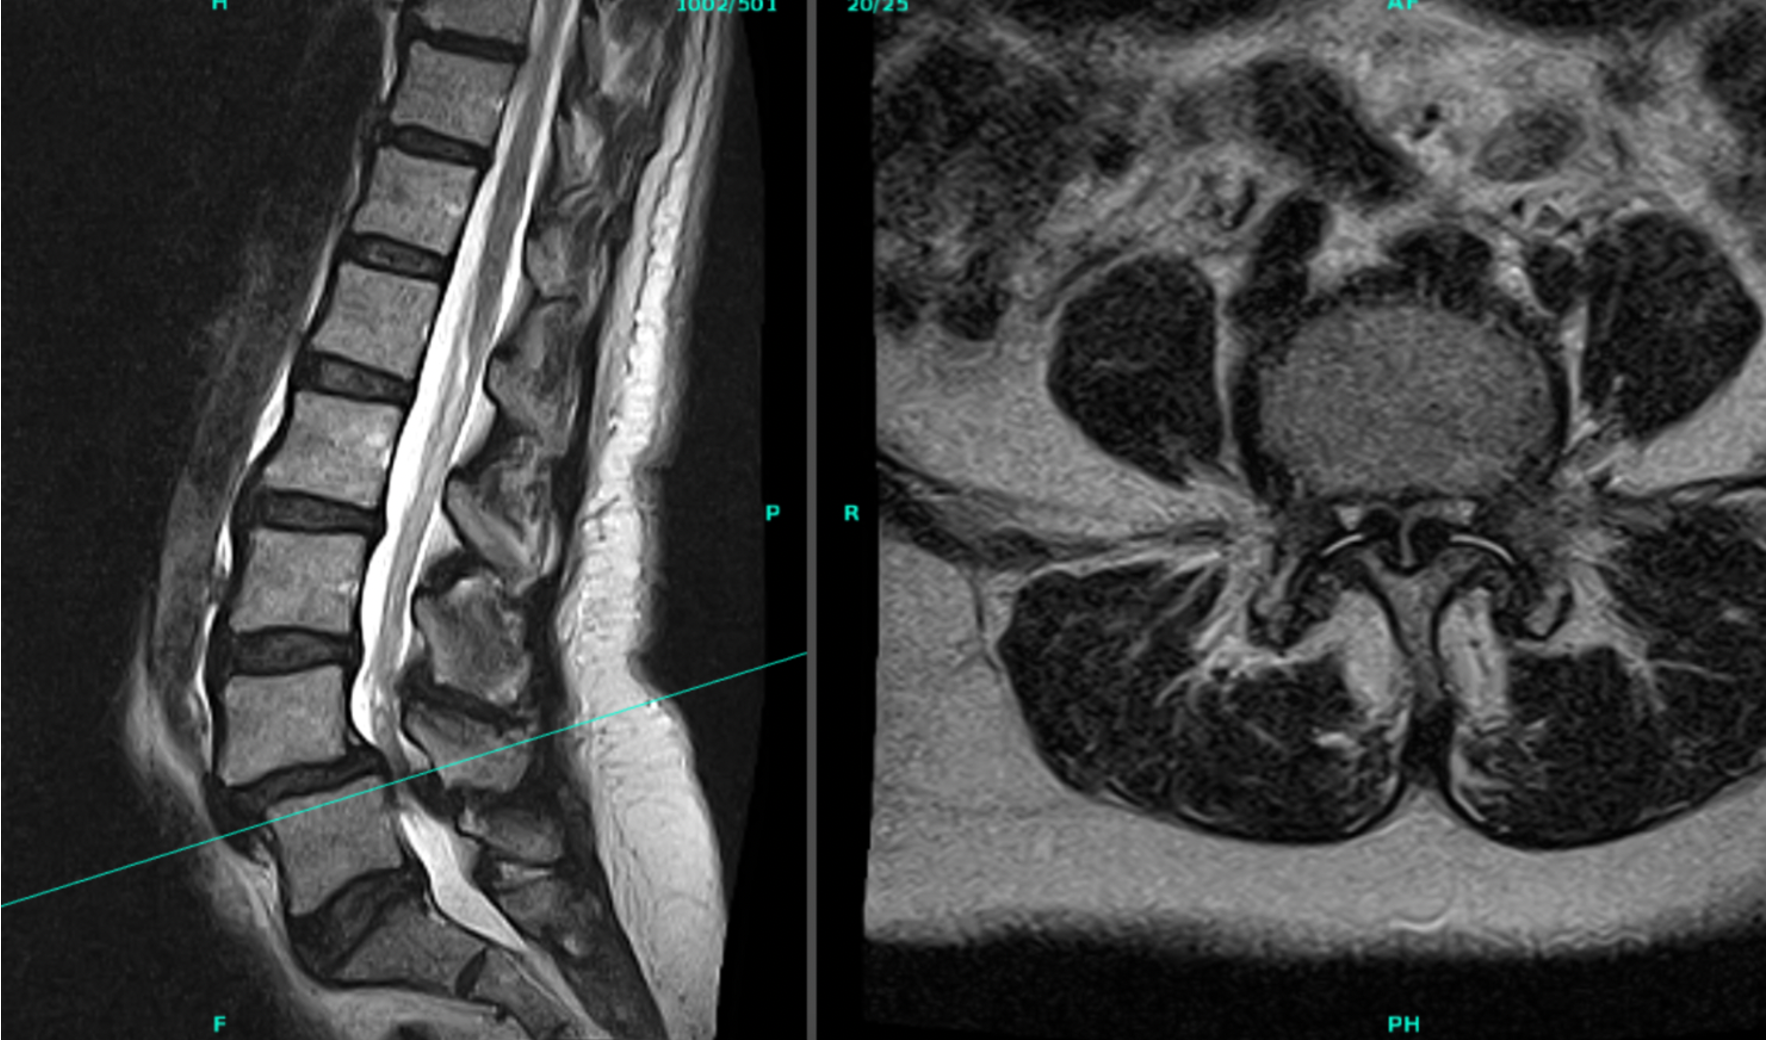

MRI scans showing images of the lower spine and a cross-section of the pelvis.

When Should Surgery Be Considered?

Fusion may be recommended when:

• Spinal instability is present

• A vertebra has slipped forward (spondylolisthesis)

• Nerve compression causes significant symptoms

• Decompression alone would not provide enough stability

For the right indications, lumbar fusion can significantly improve quality of life.